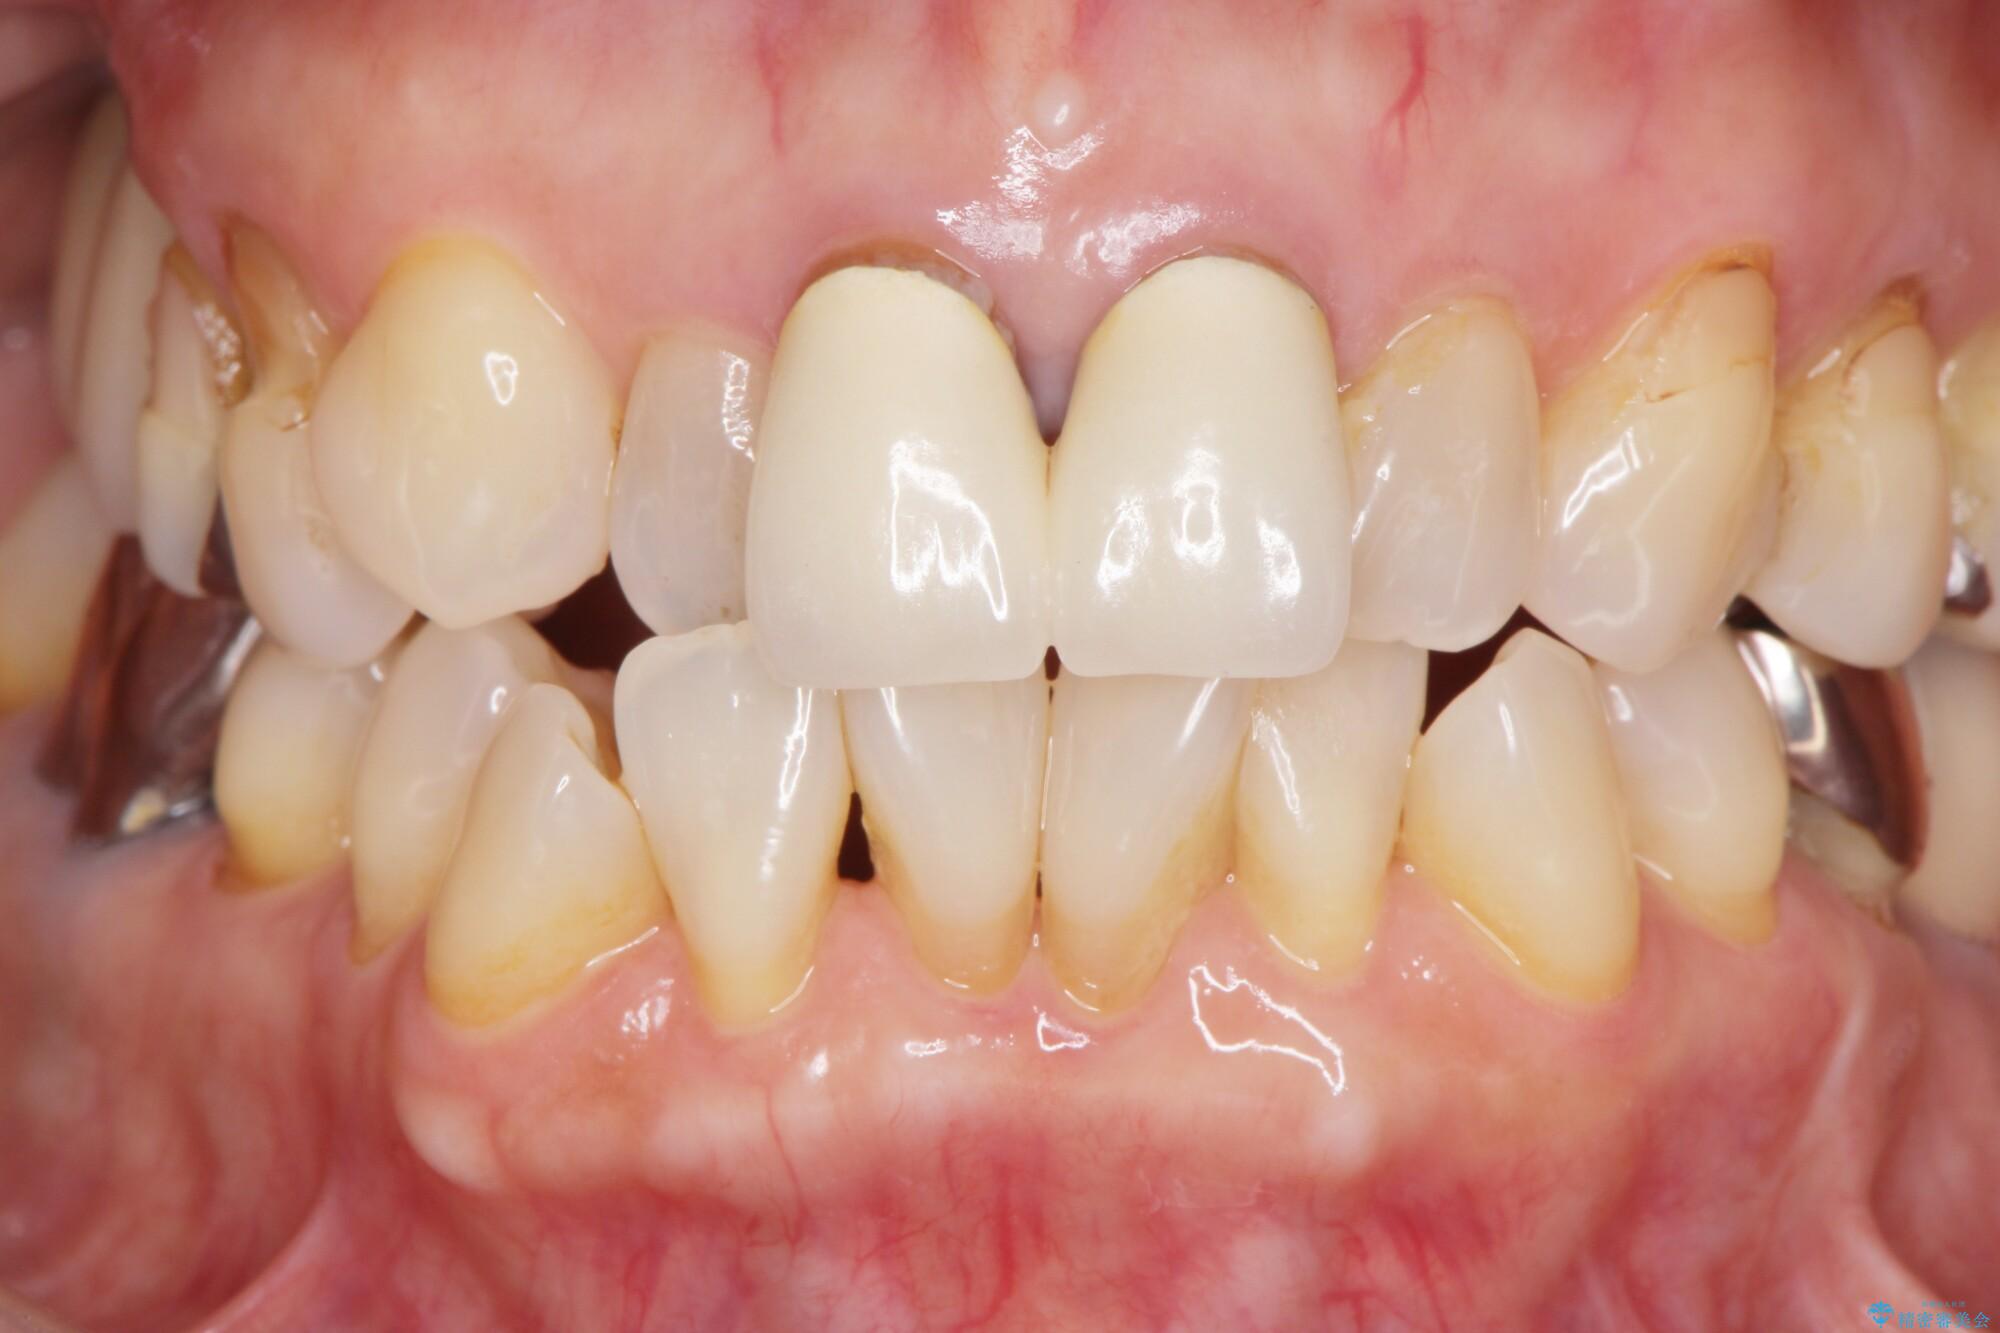

前歯の差し歯(クラウン)が黒ずんでいるとご相談にいらっしゃった患者様です。

根管治療は行わず、クラウンのやり替えのみ行います。

審美性に優れるジルコニアクラウンによる治療を計画します。